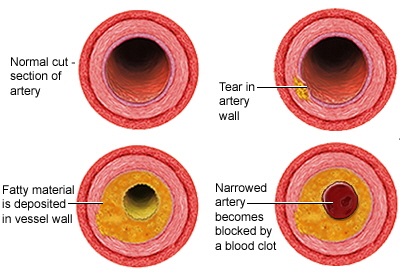

죽상경화(동맥경화) 혈전생성은 죽상경화(동맥경화)에서 비롯되며 죽종이라는 것은 혈관 안쪽에 형성된 죽처럼 끈질긴 병변입니다. 죽상경화가 그대로 커져 혈관을 폐쇄하는 경우도 있지만 대부분은 죽종에 다시 혈소판이 부착돼 혈전을 생성하고 이런 모양의 벽재혈전이 혈관을 폐쇄합니다.

혈전은 비교적 천천히 동맥의 협착과 폐쇄를 일으킵니다. 그리고 어느 정도 두께의 동맥이 폐쇄되느냐에 따라 혈전성 뇌경색과 열공성 뇌경색으로 구분합니다. 전자는 비교적 굵은 동맥(전·중·후대뇌동맥)에 발생하고 후자는 관통동맥(교합혈관이 없는 동맥)에 생깁니다.